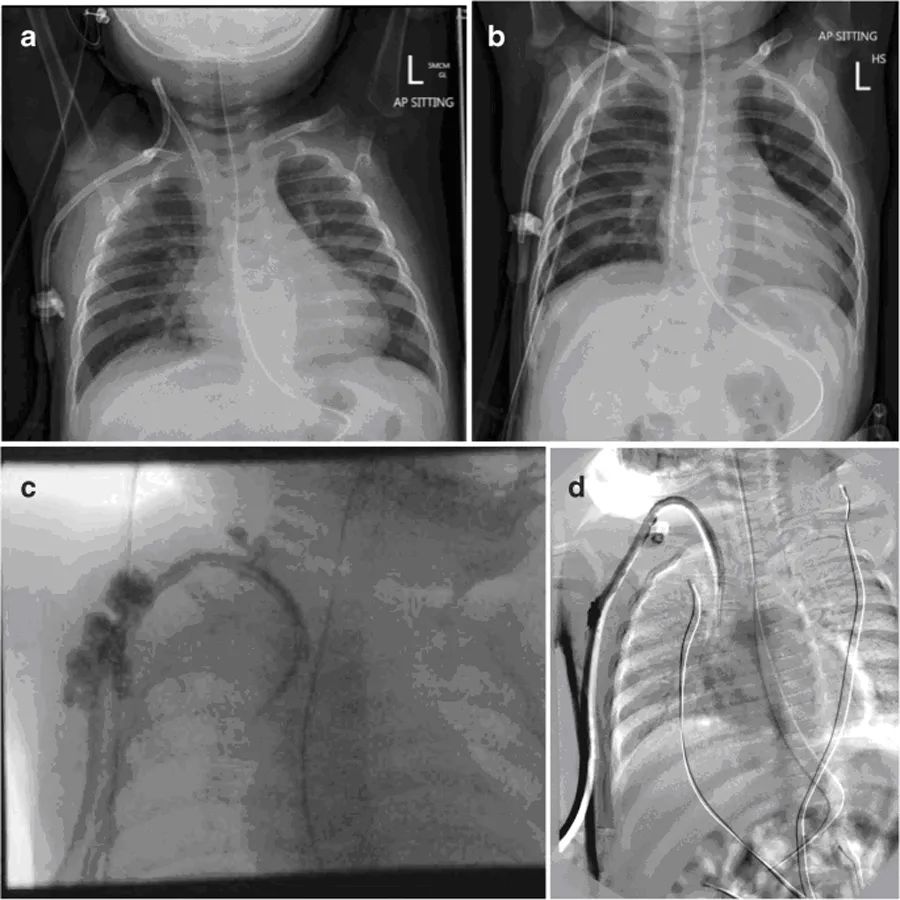

第二天,两个透析导管腔都很难抽吸,冲洗时需要高压。X光片显示导管尖端在上腔静脉中上部,提示导管位置异常(图1a)。导管流量小,无法血液透析,患者第二天返回手术室进行调整。在确认颈部入口处有扭结后,导管被重头定位。两个腔在术中冲洗和抽吸良好。患者在手术后立即开始第一次血液透析,持续2小时,患儿耐受良好,治疗成功。

在随后的血液透析过程中,发现动脉腔抽吸困难,血流速度减慢。静脉腔功能良好。置入后11天,x光片显示导管尖端在右心房内向下移动(图1b)。由于静脉回流压力高(>200mmHg)和次优最大血流量(30ml/min),血液透析提前终止。给予tPA,但没有令人满意的改善。最大血流速度可达到50ml/分钟,但回流压力仍然过高(250mmHg)。

将导管更换为Medcomp®10 Fr×15 cm分离式导管®,通过一个稍微位于前一切口内侧的新切口插入右侧颈内静脉。选择大口径、短导管,以达到更高的流速和避免导管尖端的移动。影像增强确认位置,两腔在手术室冲洗和抽吸良好。放置导管后,立即尝试血液透析,但尽管冲洗良好,动脉腔仍无法抽吸,患儿明显疼痛。影像学检查显示对比剂似乎从多个部位逃逸到周围组织中(图1c)。立即取出导管,用一个位于右心房的12-Fr剥离式鞘管通过上一个切口替换成新导管。在检查或冲洗拆除的管线时,未发现断裂迹象。影像增强确认了新透析通路的位置,在肝素封管前,两个管腔在手术室抽吸和冲洗良好。

在次日开始血液透析时,动脉压过高(>250 mmHg),血流速度不能超过30 mL/min。更换通路,之后达到50 mL/min的血流速度。然而,几分钟后,患儿表现出疼痛,并在出口处发现出血。影像学检查确认导管位置正常,但是,显示造影剂渗入周围组织(图1d)。